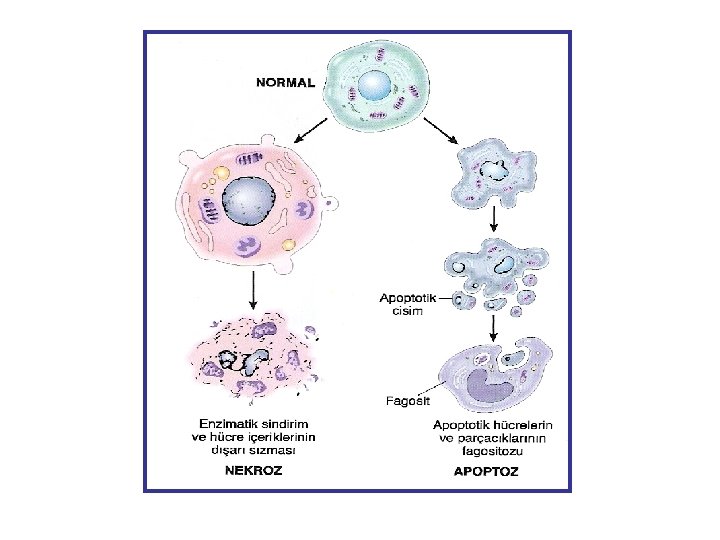

Hücre Ölümü NEKROZ: Her zaman patolojik Membran zedelenmesi şiddetli ØLizozom membran bütünlüğü bozulur ve enzimler sitoplazmaya geçer. Organeller sindirilir. ØPlazma membran bütünlüğü bozulur. Hücre içeriği dışarı çıkar ve çevrede inflamasyon yanıtı oluşur. Ana hücre ölüm yolu APOPTOZ: Çoğunlukla fizyolojik (görevini tamamlamış veya zararlı olabilecek hücrelerin ortadan kaldırılması, dokudaki hücre sayısının sabit tutulmaya çalışılması) nadiren patolojik (DNA zedelenmesi) Programlı hücre ölümü (sıkı kontrol, aktif enerji) Membran bütünlüğü tam olarak bozulmaz. İnflamatuar reaksiyon gelişmez.

Nekroz tipleri: • Koagülasyon nekrozu (Beyin dışı dokularda, hipoksiye bağlı hücre ölümünün karakteristik görüntüsüdür. ) Doku çatısı bir süre de olsa korunur. • Likefaksiyon nekrozu (Beyinde hipoksiye bağlı hücre ölümünün karakteristik görüntüsüdür + Enfeksiyöz durumlarda) • Kazeifikasyon nekrozu (Ör: tüberküloz) • Yağ nekrozu (yağ dokusunu oluşturan hücrelerin ölümündeki görüntüdür. )